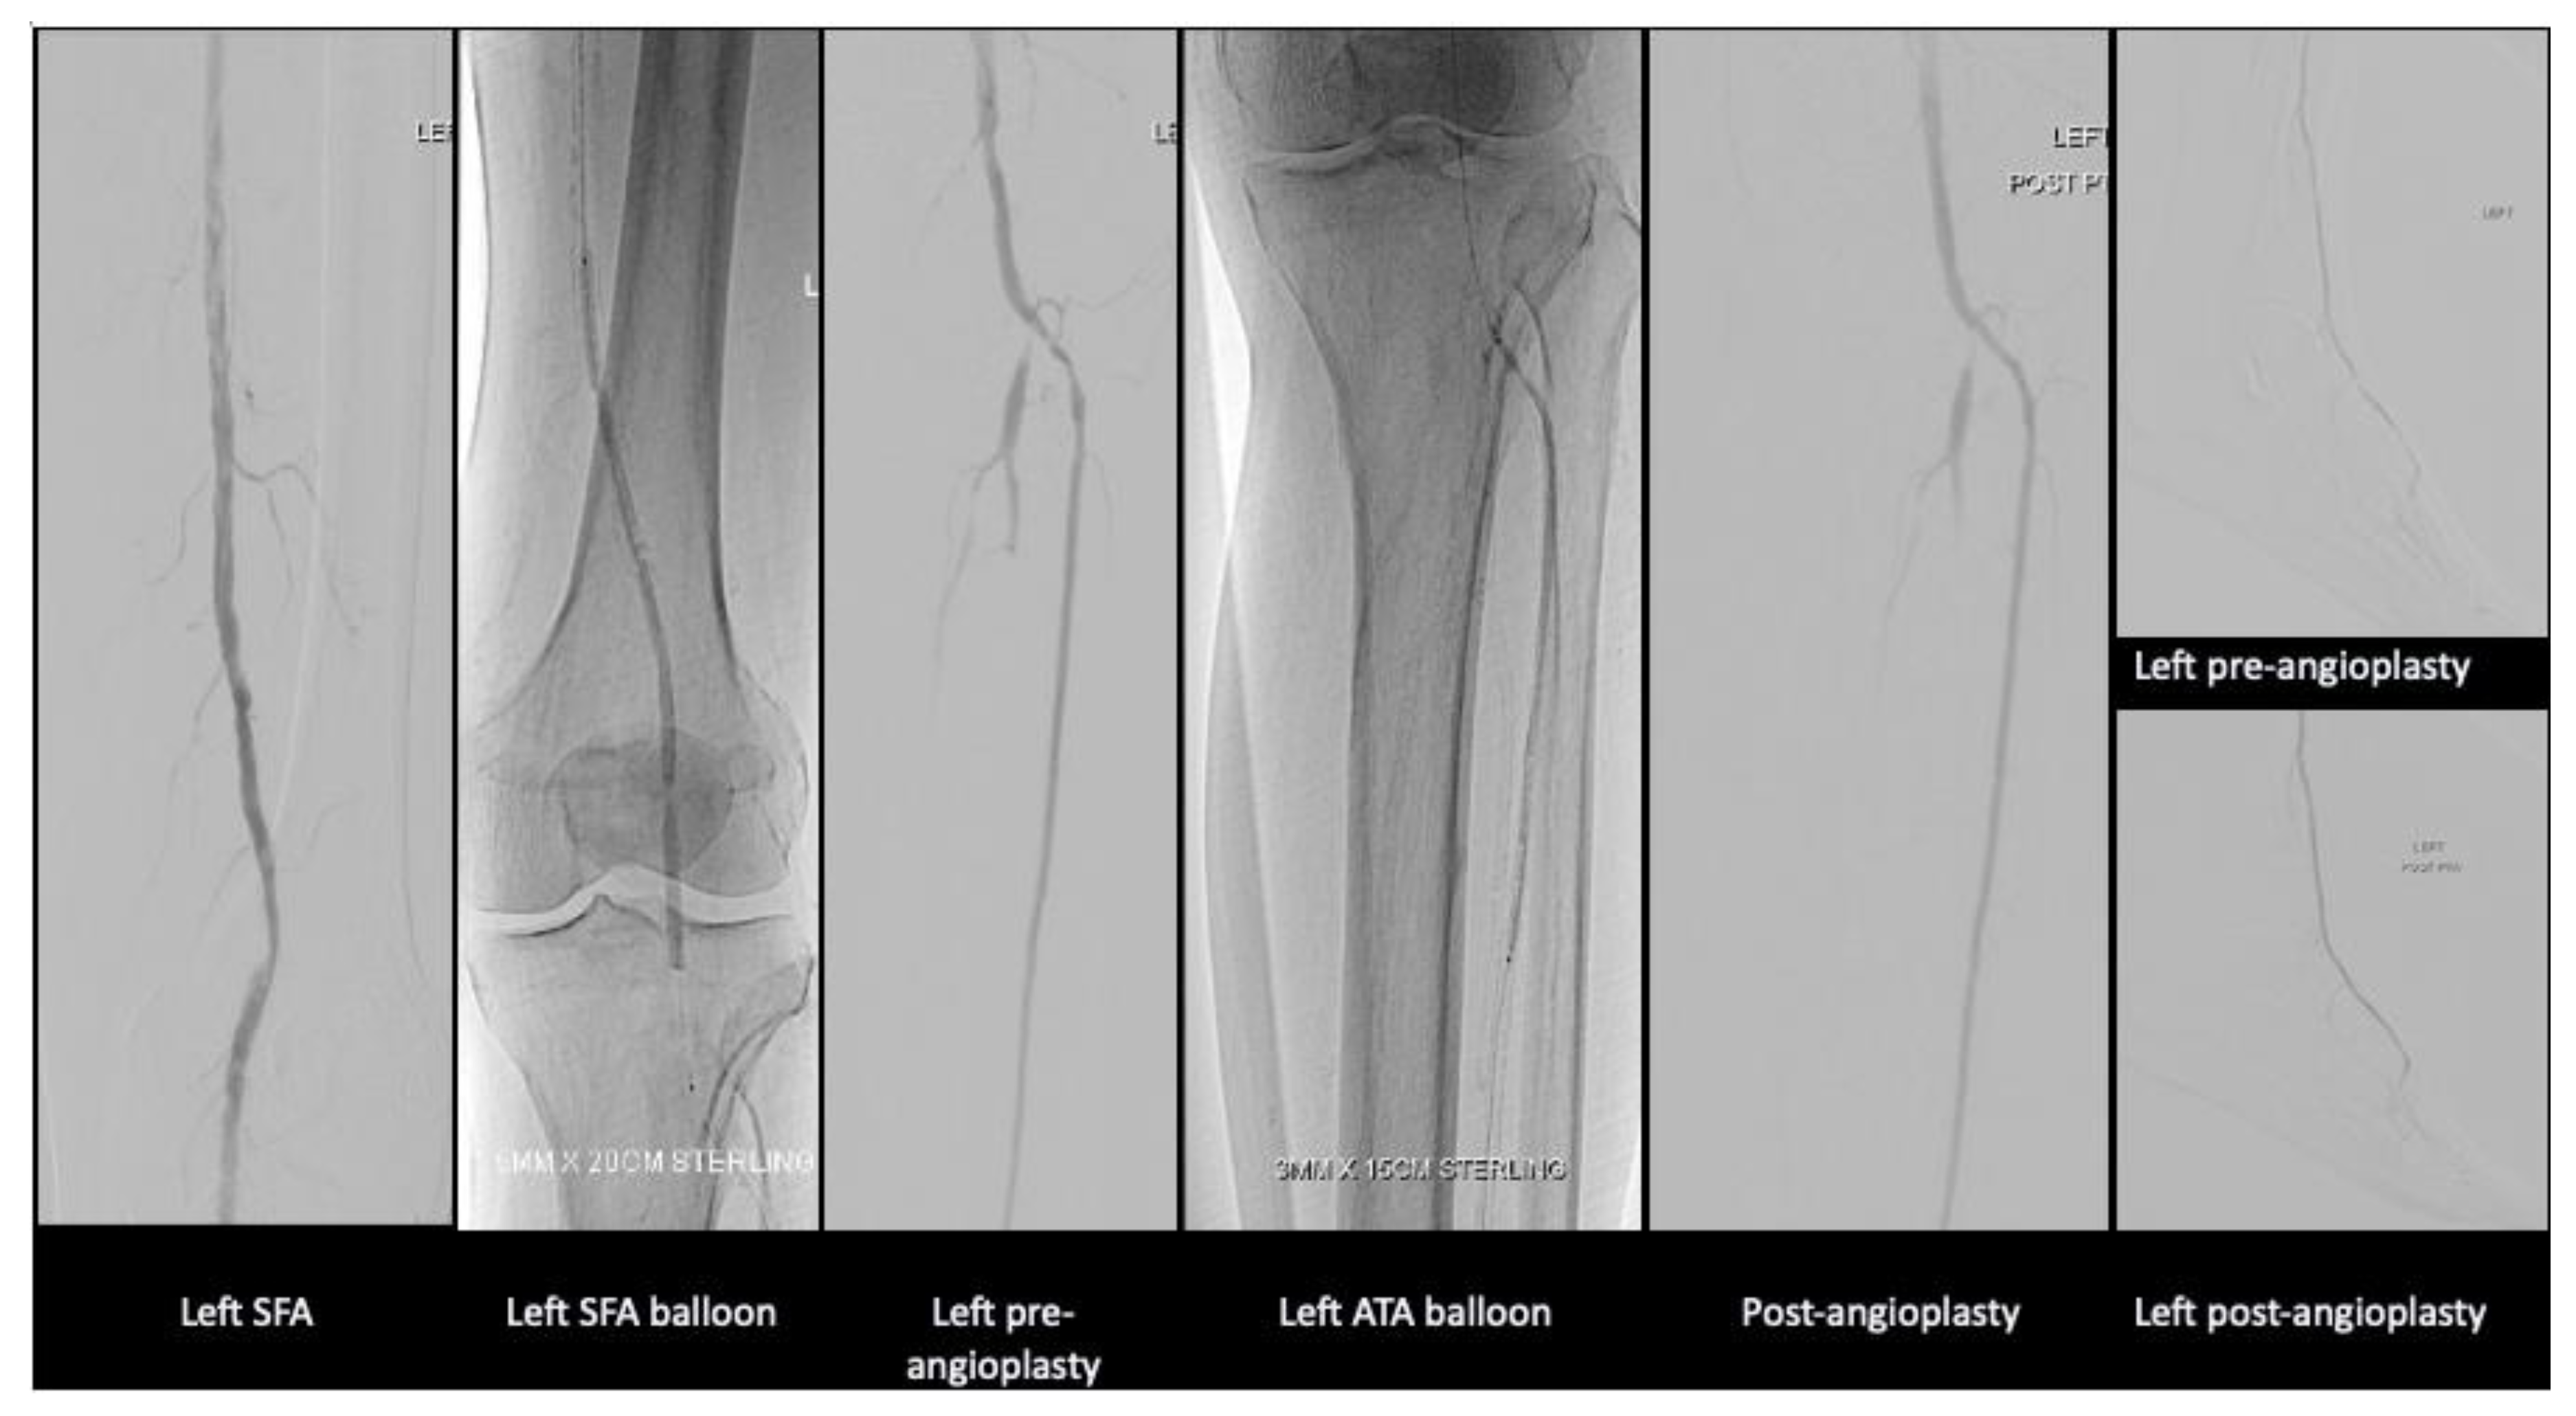

After much discussion, patient and vascular team decided to attempt limb salvage with bilateral lower limb angioplasties and fifth toe ray amputations at the same setting. Angioplasty to anterior tibial artery, posterior tibial artery, dorsalis pedis, common plantar artery was performed on the right lower limb with successful outcome. On the left lower limb, angioplasty to the anterior and posterior tibial artery was performed. Patient’s wound recovered with combination of culture directed antibiotics, vacuum dressing and motivation from a supportive family.

Figure 4. Angioplasty images of the right lower limb.